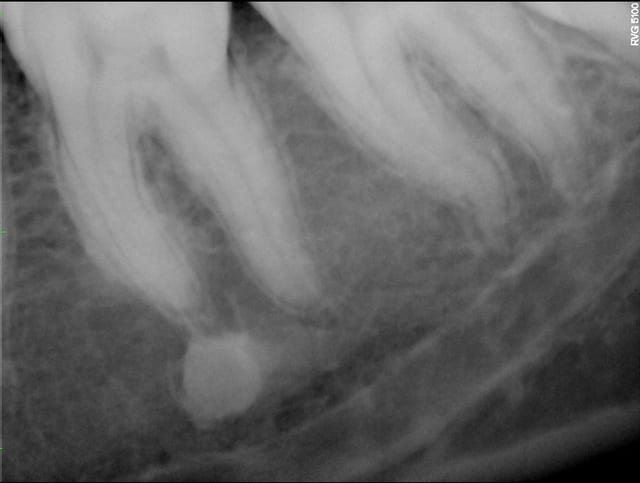

A priori, vu la densité, une traversée d'os cortical. Rien de spécial à faire. Exemple en pièce jointe. Refaire une radio dans 1 an pour le principe.

Corticale2 gt3604 - Eugenol

Corticale1 tfvxho - Eugenol